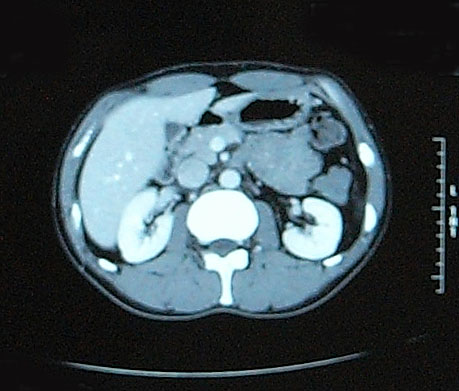

【単純CT】

問題なし! 【腫瘍マーカー】 HCGβ:<0.1 問題なし! 次は9月!

問題なし! 【腫瘍マーカー】 HCGβ:<0.1 問題なし! 先週検査でした。 今日はその結果。 今日は珍しく先生が寝ぼけていました(笑)。 次回のレントゲン検査の受付票を何回も出し間違えた。 1回目:診察後清算も済み帰ろうとした所で俺が気がついた。「これ、画像データCDR作成申込書じゃん・・・」 2回目:受付で上記を伝え、看護婦さん:「すいませ~ん!これで大丈夫ですか?」 確認すると今度はXP検査受付票なので「OKです!ありがとうござ・・・ん?!?これ検査日が今日です・・・・」 看護婦さんダッシュで戻っていきました。 3回目:看護婦さん:「今度は~~」 俺:「間違いないです!」 看護婦さん:「先生寝ぼけてるんですよぉ~」 次は3月!

問題なし 【腫瘍マーカー】 HCGβ:<0.1 問題なし 【中性脂肪】 219→137 基準内(38-193)に入った 今回、検査画像をデータでもらってきた。 後腹膜の転移した箇所の前後4枚を2003年から2010年まで並べてみた。 http://gomatsushita.gozaru.jp/ct/album/index.html 2006/7/18の画像を見ると腫瘍がハッキリ見える。 BEP2クール後の9/27の画像では明らかに縮小もしくは消滅。

【CT画像】

単純CT:特に変化を認めず。 【腫瘍マーカー】 HCGβ:<0.1 問題なしでした! 今日は画像はありません。 理由は、病院側でデジタル化が進んでいて、PCモニターでの画像確認となったからです。 今日はフィルムも用意されませんでした・・・・。 先生曰く、そのうちフィルムもなくなるだろうと。 そのときにはCD-R等に焼く対応もするようになっているはずだと。 早くデータで画像がほしい。その時はたくさんアップしますw。 次回は2月です。

今回からCTの造影剤はありませんでした。

勘違いしてた・・・ なので単純CT。 横になって撮るだけなので非常に楽ですね。その分撮影される画像も解像度が低くなりますが・・・ しかし、思えば2005年末頃の単純CTからリンパ転移が疑われ始め、その次からはずっと造影剤を使用したCTだったわけだ。 2008年末の今、やっとそこへ戻ってきたという感じがした。 検査後の帰り、病院の最寄り駅のパン屋で朝食。 改札横に店があるのでガラス越しに行き交う多くの人を眺めながら思う。 2006年の入院中、ヨメも色々思いながらここを通ったんだろう、と。 何ヶ月も。 暑い日も雨の日も。 ただただ「感謝」あるのみです。 本日の検査結果は12/8。